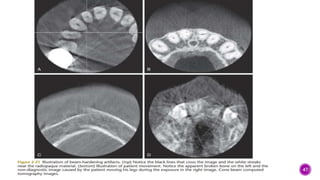

 The recent introduction of cone-beam computed tomography (CBCT) into the

medical field has allowed the nondestructive investigation of internal

structures at relatively low cost and radiation exposure.

 This technology has become very popular in the past decade and has found

its way into many private practices. This modality is ideal for imaging hard

tissues. Artifacts due to beam hardening and motion artifacts are to be

avoided . The radiation dose from CBCT is considerably higher than that from

a periapical radiograph. It is also very hard to determine the radiation dose in

general from CBCT since it depends on exposure settings (kVp, mA, and

exposure time), field of view (the size of the volume, which is determined by

the size of the coneshaped x-ray beam), and the resolution of the image (the

details). Justification to expose pediatric patients to CBCT should not be

taken lightly